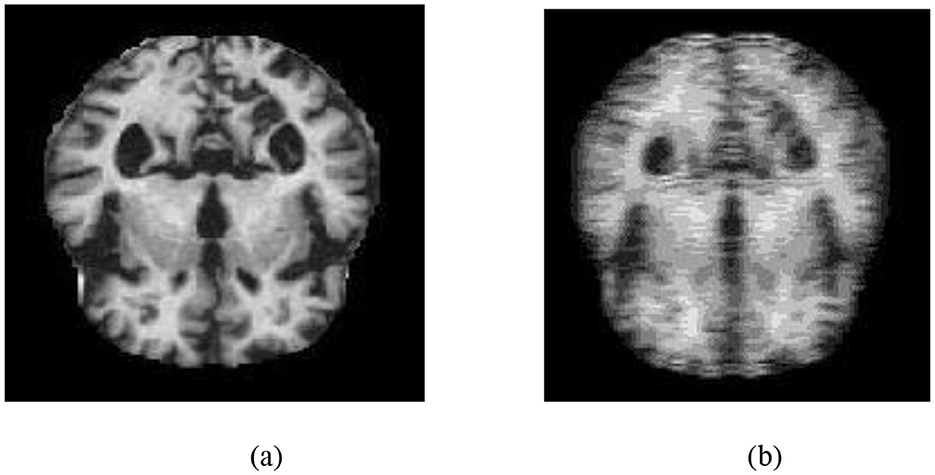

The angle of orientation of each pixel varies from −90 degrees to +90 degrees in 1-degree increments. Hence, for each frequency factor with a spatial factor, there is a 180-degree range of orientations, which creates 180 GK. These 180 GK are linearly convolved with the input source brain MRI image, producing 180 Gabor output images. These 180 Gabor output images are combined into a single Gabor image by selecting the maximum pixel intensity in each image. Figure 3 depicts an sMRI image of an AD subject and its corresponding Gabor-transformed image.

Figure 3. (a) T1-weighted sMRI image of an AD subject. (b) Corresponding Gabor-transformed image highlighting texture and frequency-domain features.